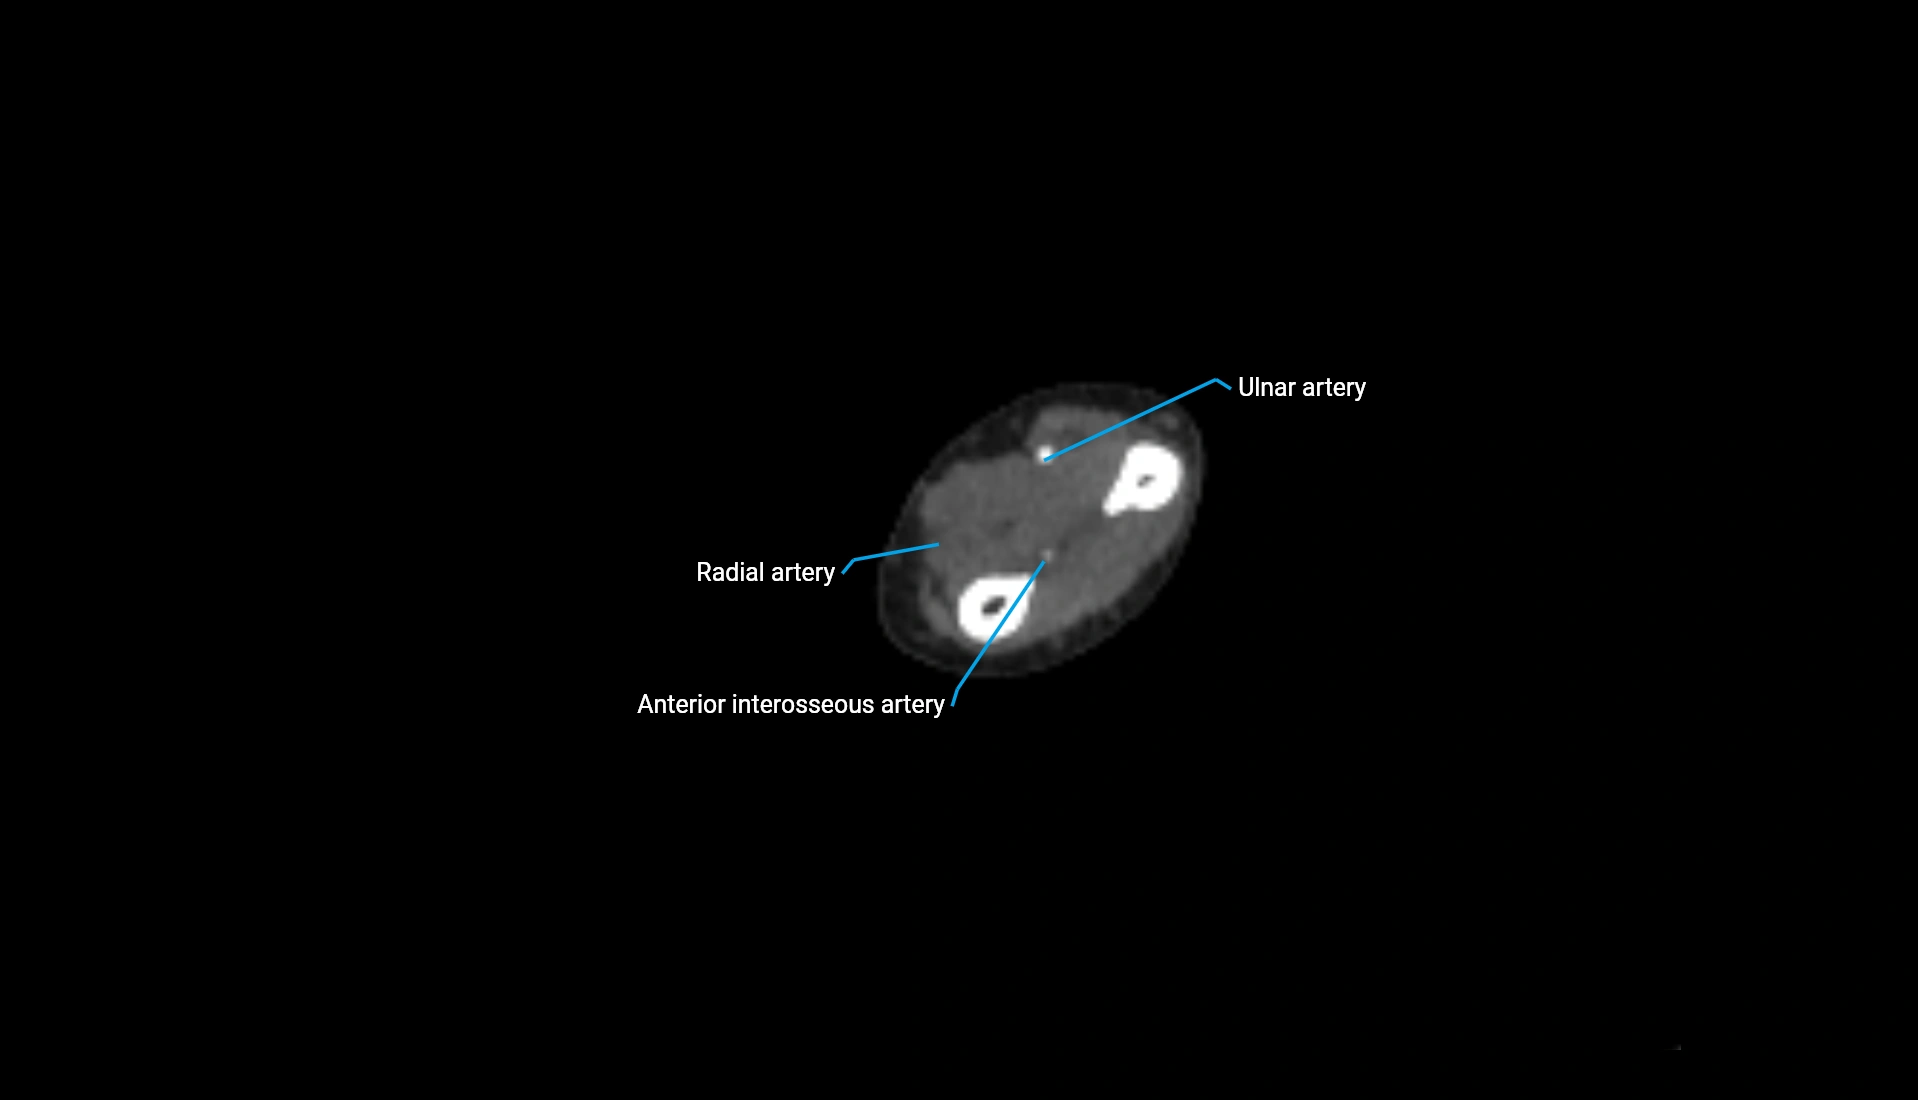

CT Appearance

Non-Contrast CT:

• Cortex: High-density, sharply defined

• Subchondral bone: Dense cancellous matrix

• Articular surface: Smooth concave contour articulating with the capitellum

• Excellent for evaluating bone integrity, alignment, and subtle fractures